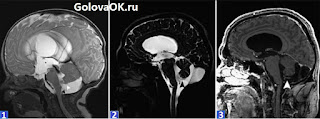

Карман блейка у плода

Карман блейка у плода 116 фотографий